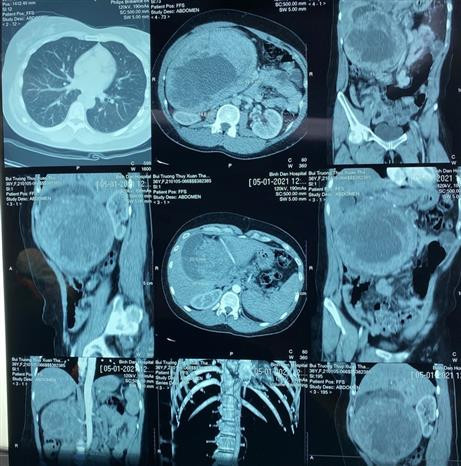

Bệnh viện Chợ Rẫy bóc tách khối u tuyến tụy lớn nhất từ trước đến nay ảnh 2Hình ảnh trên phim cho thấy bệnh nhân có một khối u đầu tụy khổng lồ, chiếm hết ổ bụng. (Ảnh: Đinh Hằng/TTXVN)